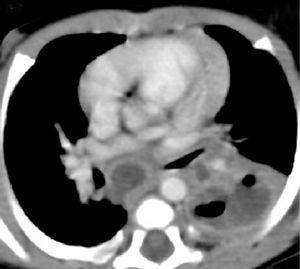

Se practica TC helicoidal multicorte observando un patrón micronodular difuso asociado a condensaciones en los segmentos 1 del lóbulo superior derecho, 6 y 9-10 del lóbulo inferior izquierdo con cavitaciones.

Tras administrar contraste intravenoso se identifican múltiples adenomegalias mediastínicas, de tamaño superior al centímetro de diámetro, en los espacios paratraqueal derecho, ventana aortopulmonar, subcarinal e hiliar izquierdo que realzan periféricamente con centro hipoatenuado (fig. 2).

Figura 2.Corte axial de TC tras la administración de contraste intravenoso. Adenomegalias subcarinal e hiliar izquierda con realce periférico y centro hipodenso por necrosis caseosa. Infiltrado en lóbulo inferior izquierdo cavitado y engrosamiento pleural asociado.

Los hallazgos radiográficos orientan hacia una forma de tuberculosis avanzada, aunque la prueba de tuberculina fuese negativa.

La TC es la prueba gold standard en el diagnóstico de afectación ganglionar mediastínica 5. Cuando la adenopatía alcanza los 2 cm, característicamente muestra un realce periférico tras la administración de contraste intravenoso, siendo el centro de la lesión marcadamente hipodenso por necrosis caseosa. Adenopatías mayores de 1 cm se consideran definitivamente patológicas 5.